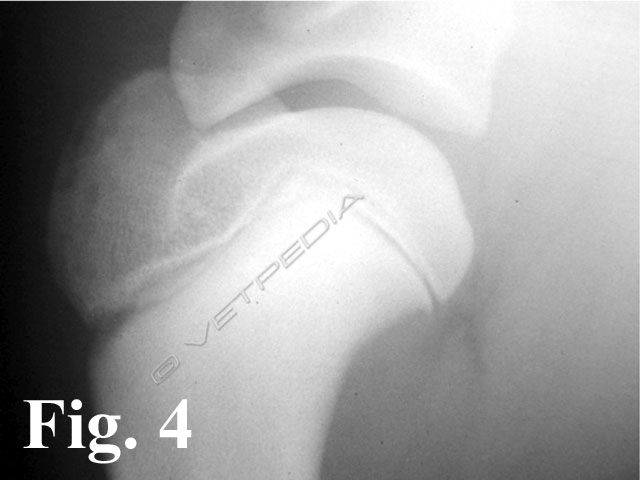

In caso di osteocondrite dissecante (OCD) si verifica una fissurazione nella parte ispessita della cartilagine ed il sollevamento di un lembo osteocondrale, seguito dall’esposizione di osso subcondrale (Fig. 1). Il movimento eccessivo o i microtraumi derivanti dalla normale attività fisica possono determinare il distacco completo del lembo osteocondrale, che diviene corpo libero articolare. Quest’ultimo può andare incontro a destini differenti: molto raramente può riassorbirsi, può dislocarsi nel fondo cieco caudale (cul di sac) o prossimalmente nella doccia bicipitale. Il lembo può accrescersi e calcificare traendo nutrimento dalla vascolarizzazione sinoviale e divenire visibile radiograficamente (Fig. 2). Il contatto del liquido sinoviale con l’osso subcondrale scatena un insieme di reazione biochimiche e biologiche che porta alla formazione di sinovite, momento in cui generalmente si osservano i primi sintomi clinici. Anche il lembo osteocondrale quando diviene corpo libero può svolgere un’azione continua d’irritazione e divenire concausa dello sviluppo di sinovite. Il difetto cartilagineo viene riparato dalla formazione di fibrocartilagine.

Alla visita ortopedica apprezziamo algia all’esecuzione dei movimenti passivi dell’articolazione. Con il cronicizzarsi della lesione osserviamo un diverso grado di ipomiotrofia dei muscoli della spalla. Il sospetto diagnostico emesso dalla visita clinica viene confermato mediante l’esecuzione di uno studio radiografico dell’articolazione della spalla. Per emettere una diagnosi è generalmente sufficiente eseguire una proiezione medio-laterale della spalla, avendo l’accortezza di esercitare una trazione sulla zampa in modo da scostare l’articolazione dalla sovrapposizione radiografica dello sterno. Considerando la frequente bilateralità della lesione, è doveroso eseguire un controllo dell’arto contro laterale, in modo da non trascurare quelle lesioni ancora clinicamente asintomatiche o paucisintomatiche. L’esame radiografico evidenzia un difetto del profilo del terzo caudale della testa omerale (Fig. 3). In alcuni casi è possibile visualizzare il lembo osteocondrale sollevato ma ancora in sede (vedi Fig. 1), in altri casi si può osservare solo un aumento della radiotrasparenza dell’osso subcondrale, più o meno esteso. Alcune forme iniziali di osteocondrosi (OC), non ancora evolute in osteocondrite dissecante (OCD), si manifestano radiograficamente come dei piccoli appiattimenti del profilo tondo della testa omerale, senza modificazioni della densità omogenea sub condrale (Fig. 4).

La corretta diagnosi di queste forme iniziali ci consente di indirizzare il paziente verso un approccio chirurgico o conservativo. In caso di diagnosi di OC, è consigliabile monitorare radiograficamente la lesione, con controlli a distanza di circa 2/3 settimane, in modo da valutarne l’evoluzione: guarigione spontanea versus formazione e sollevamento del lembo osteocondrale. Nei casi in cui la lesione è localizzata medialmente, la proiezione medio-laterale neutra potrebbe non consentirci di evidenziare il difetto osteocondrale o di sottostimarne l’estensione (Fig. 5a). E’ consigliabile a tal proposito eseguire una proiezione medio-laterale con rotazione esterna dell’arto, in modo da esporre al fascio radiogeno tangente anche le lesioni localizzate nel comparto mediale (Fig. 5b). Un’altra evenienza è rappresentata dalla migrazione del lembo osteocondrale che, come precedentemente accennato, nei casi più fortunati potrebbe andare incontro a riassorbimento spontaneo oppure comportarsi da “topo” o “tofo” articolare (Fig. 6). La sede dove più frequentemente tende a localizzarsi è rappresentata dal recesso caudale dell’articolazione (vedi Fig. 2), in casi meno fortunati potrebbe migrare nel comparto craniale, più precisamente nella doccia bicipitale, e determinare un’irritazione meccanica al tendine del muscolo bicipite brachiale. In quest’ultimo caso i sintomi dipenderanno dallo sviluppo di una tenosinovite bicipitale.